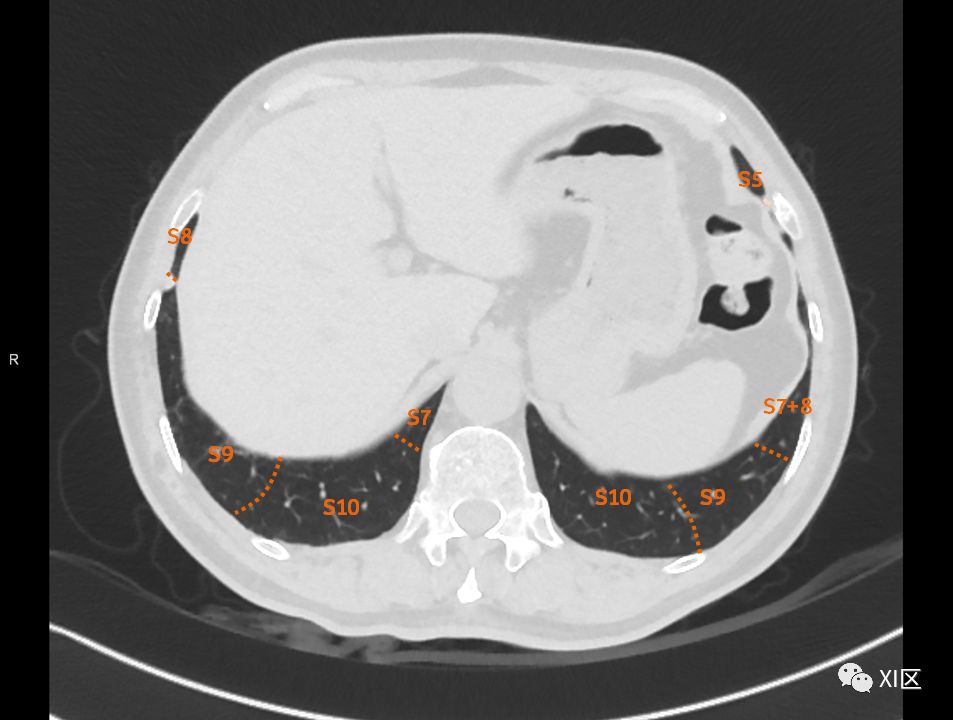

肺的断层分段示意图

在进行肺的分段时,可以上下观察浏览,沿着相应气管的走形可以更容易准确地进行分段。